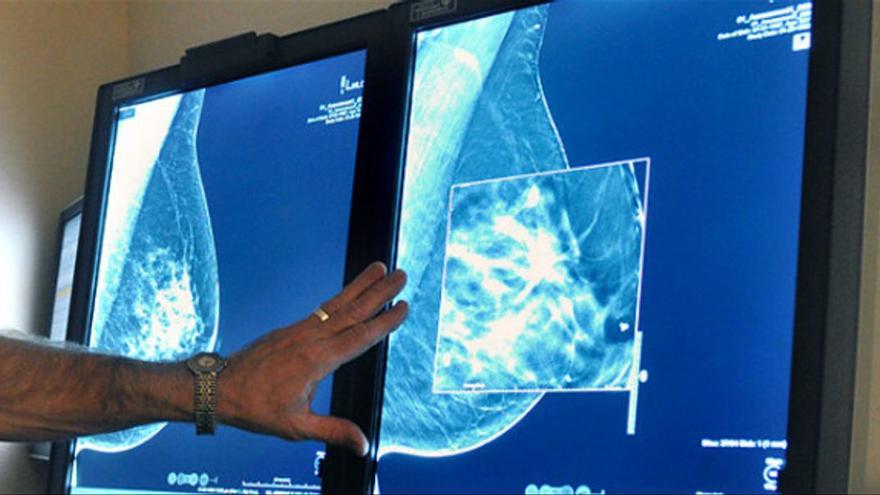

Una mútua privada ha indemnitzat amb 140.000 euros una dona pel retard en el diagnòstic d'un càncer de mama, després d'un acord entre les parts. La pacient va presentar episodis de secreció hemorràgica a través del mugró durant el febrer del 2016, quan estava embarassada, i va informar el seu ginecòleg. Els especialistes no li van fer una mamografia assegurant que podia comportar un risc per al fetus. Un any després, se li va diagnosticar un carcinoma infiltrant al pit. Aquest retard en el diagnòstic ha suposat un tractament més radical i l'extensió de la malaltia fins a metàstasi, segons ha informat el Defensor del Pacient, associació a què està adscrita la lletrada de la demandant.

Aquesta associació ha recordat que hi ha reiterada literatura científica que defensa que un fetus pot tolerar la poca quantitat de radiació emesa en una mamografia, sense que això comporti cap risc. Afegeix que la dona tenia importants antecedents oncològics familiars, així com una clínica reiterada d'hemorràgies a través dels mugrons. Per això, defensa que no haurien d'haver-se escatimat les proves necessàries, ni posposar-les perquè estigués embarassada o, més tard, per donar el pit al seu fill. Argumenta que el que era prioritari era fer un diagnòstic precoç o, com a mínim, advertir la pacient dels riscos que corria si no es feia.

El Defensor explica també que quan es va decidir fer-li una biòpsia es va informar la dona que el material obtingut era insuficient per al diagnòstic, però, tanmateix, es va interpretar la prova com un resultat negatiu per cèl·lules malignes.